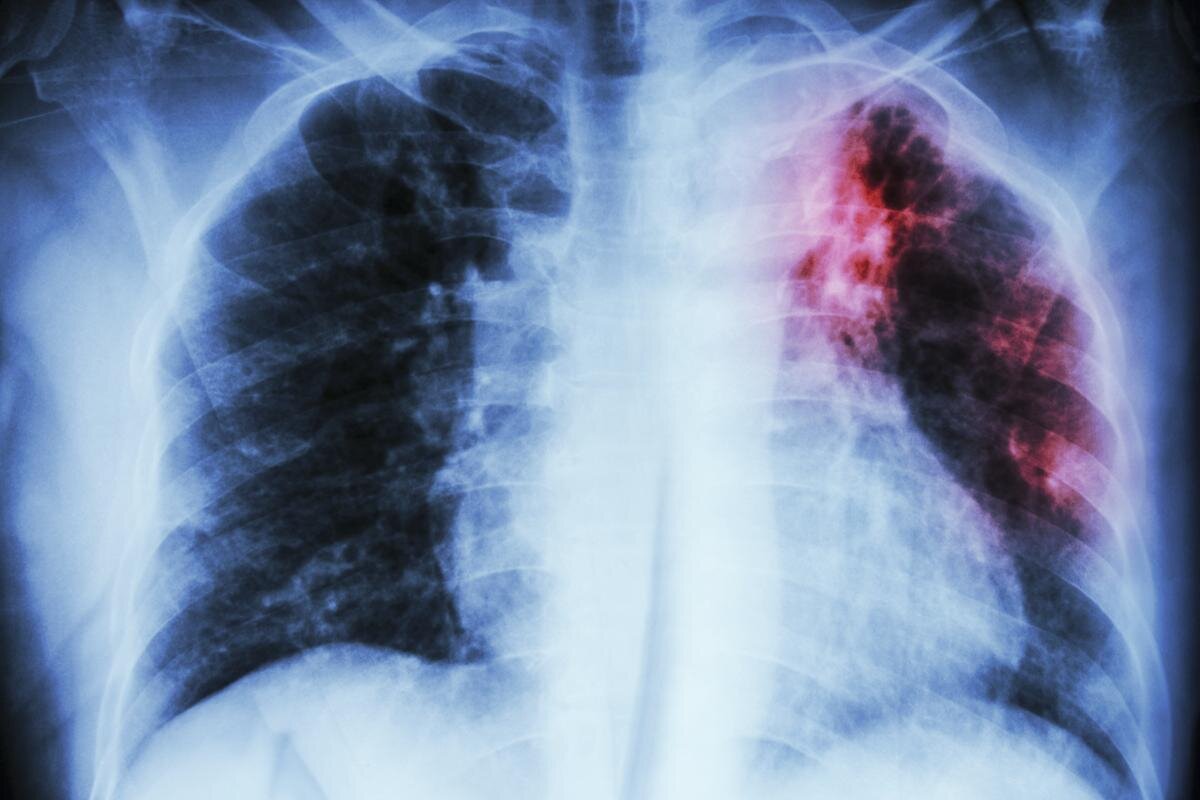

В одной из школ Приморья произошло массовое заражение детей туберкулезом

Сотрудница школьного пищеблока, которая заразила детей в одной из школ Дальнегорска Приморского края, оказалась ВИЧ-положительной. Это стало известно благодаря информации, распространенной через Telegram-канал «Октагон. Восток». По данным источника, ответ на запрос депутата Государственной думы Алексея Корниенко в Роспотребнадзоре указал на сотрудницу пищеблока как источник распространения заболевания. Эта женщина работала у предпринимателя, который обеспечивал питанием образовательное учреждение. Согласно информации из Telegram-канала, у женщины был диагностирован туберкулез в 2005 году, а ВИЧ – в 2019-м. Однако, несмотря на эти обстоятельства, она была допущена к работе после медицинского осмотра в конце 2022 года. При проверке властями были выявлены нарушения санитарных правил и норм по профилактике туберкулеза как в школе, так и в городской больнице, а также у предпринимателя, который поставлял питание. В результате, предприниматель Юрий Кононенко и его сотрудница Надежда Стожарова